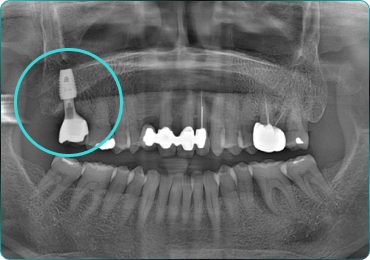

67세 여성

After